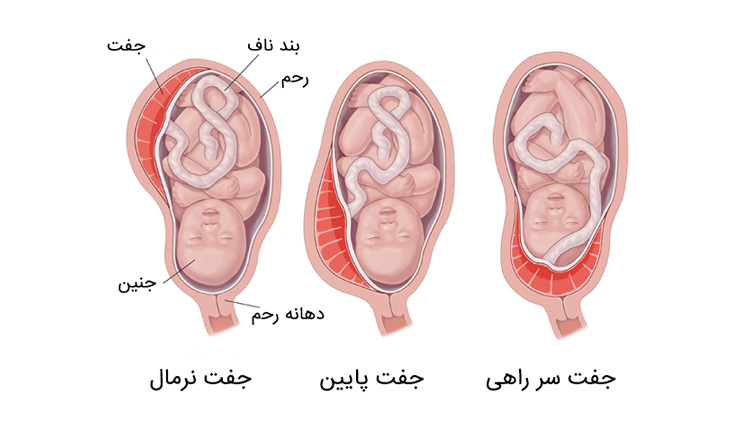

جفت سرراهی یا پلاسنتا پرویا

جفت ساختاری است که در طی بارداری در داخل رحم رشد میکند. جفت، اکسیژن و مواد غذایی مورد نیاز برای رشد جنین را فراهم میکند و مواد زائد را از خون جنین دور میکند. وقتی جفت به جای جایگزینی در دیوارهی رحم، روی قسمتی یا همه دهانهی رحم جایگزین شود به آن جفت سر راهی میگویند. جفت سر راهی میتواند زمان زایمان جلوی حرکت جنین به سمت دهانه رحم و کانال زایمان را بگیرد. پلاسنتا پرویا یا جفت سر راهی ممکن است در ۵ درصد از بارداریها رخ بدهد.